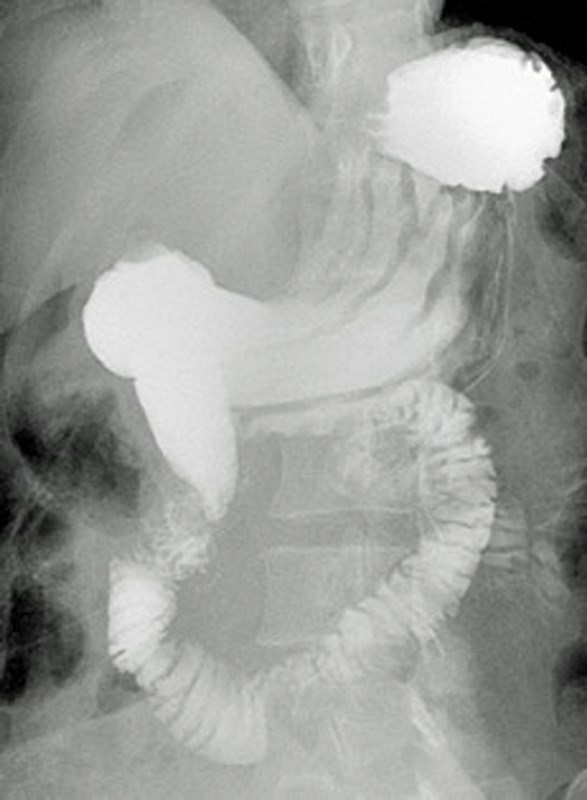

Superior mesenteric artery syndrome is a rare cause of intestinal obstruction. The condition results from compression of the duodenum between the aorta and the superior mesenteric artery, which causes an impairment of gastric emptying and associated chronic symptoms. There is a need to objectively assess the severity of gastric-emptying disorder in these patients post-treatment to assess the efficacy of the conservative or surgical management. We report here a case of a patient where the radionuclide gastric-emptying study was crucial in monitoring the effectiveness of surgical management of this syndrome.